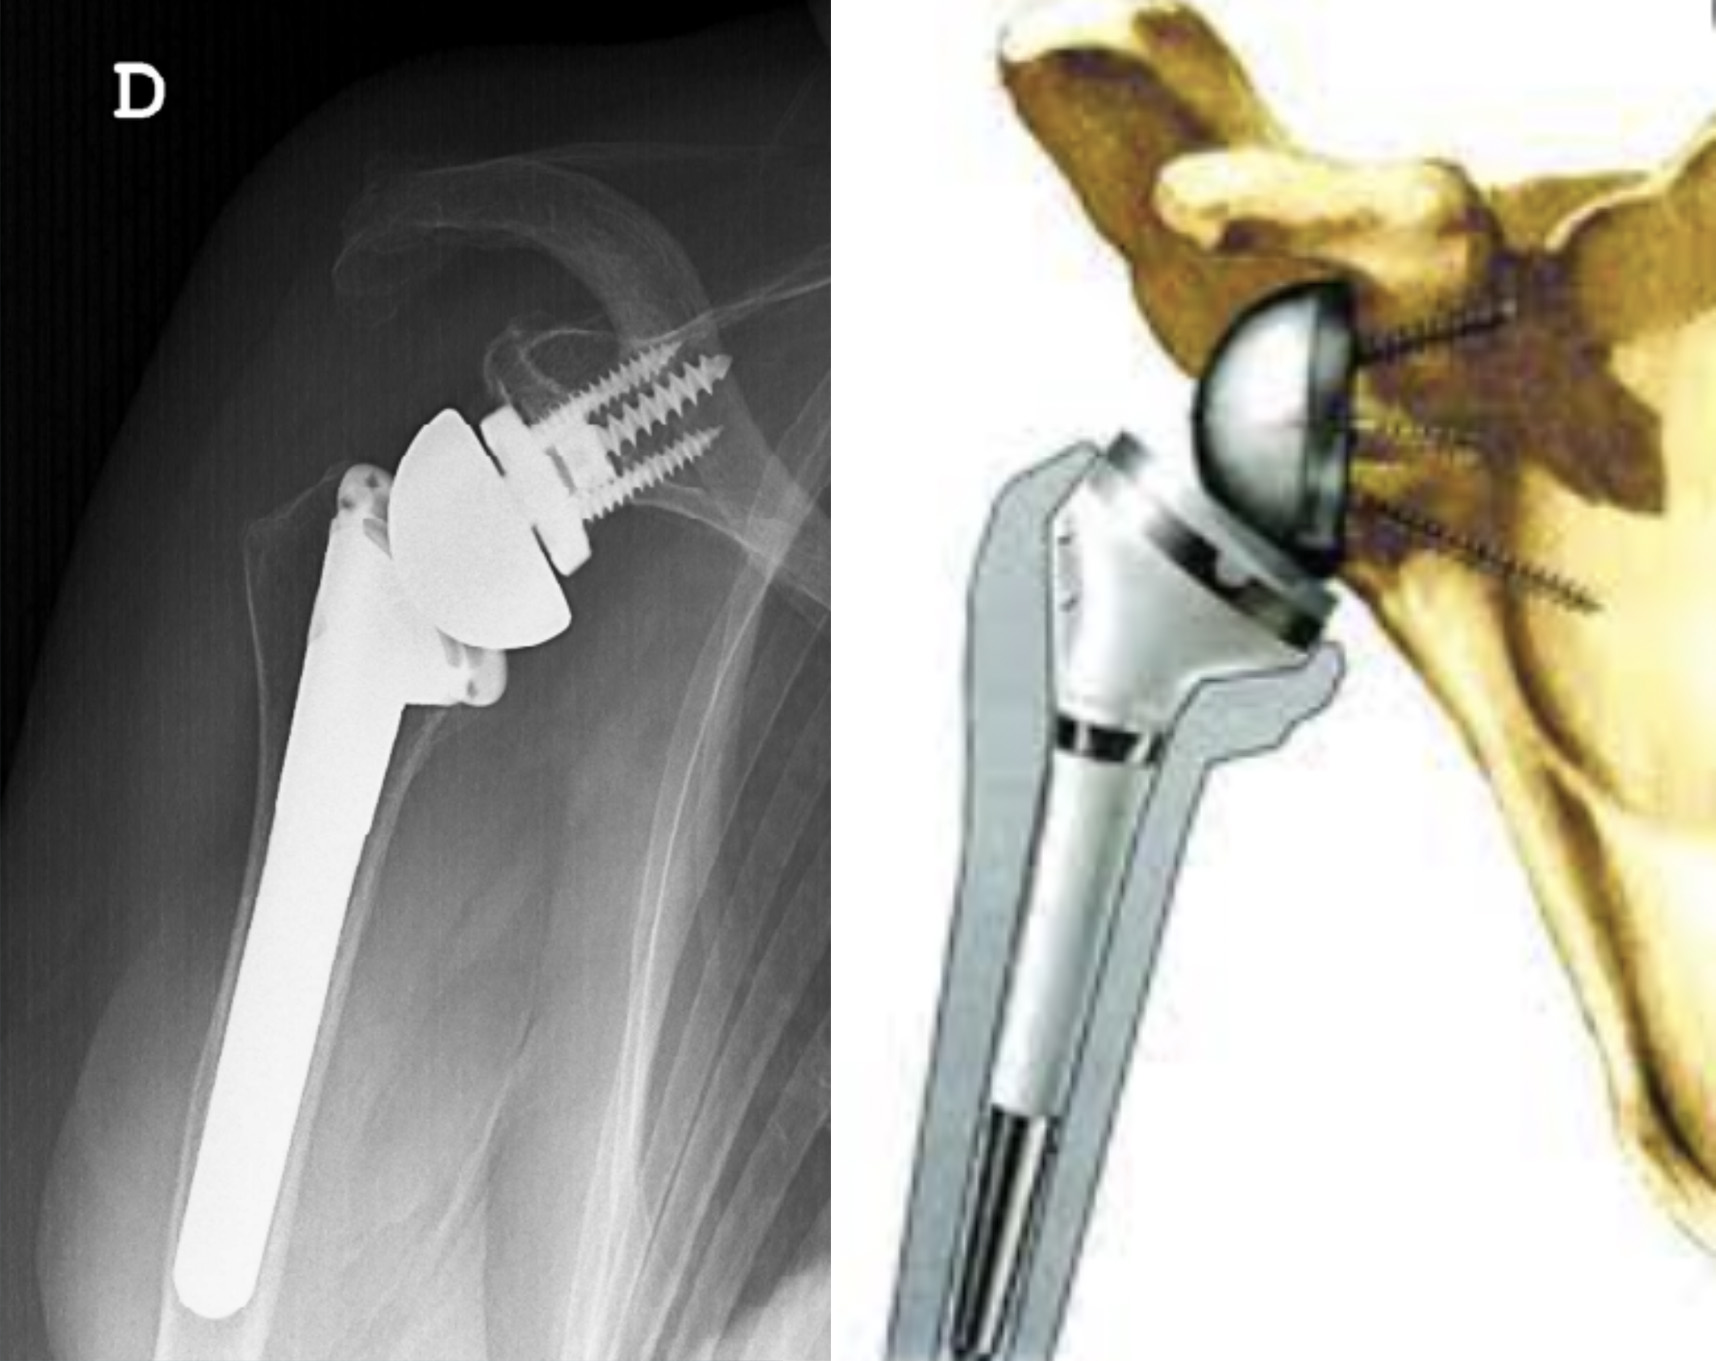

Uma artroplastia total do ombro invertida (PTO invertida) é uma tecnologia mais recente que utiliza uma substituição “não anatômica” do ombro em pacientes com artrose no ombro e sem músculos e tendões da coifa dos rotadores normais. Esta prótese também pode ser usada como procedimento de revisão para cirurgias de próteses anatómicas que falharam ou em pacientes idosos com fraturas do úmero proximal em que não se pode fazer osteossíntese (devido à perda de osso ou em fraturas cominutivas). (Fig. 2)

Numa PTO invertida a esfera do ombro (cabeça do úmero) é substituída por uma cavidade e a cavidade do ombro (glenoide) é substituída por uma esfera. Isto permite que o músculo deltoide atue em um fulcro fixo e mais longo e tenha mais vantagem mecânica, podendo assim elevar o braço sem uma coifa dos rotadores normal. A prótese fica fixa no lugar usando parafusos na parte esférica e cimento ou crescimento ósseo na parte da haste (fig. 5).